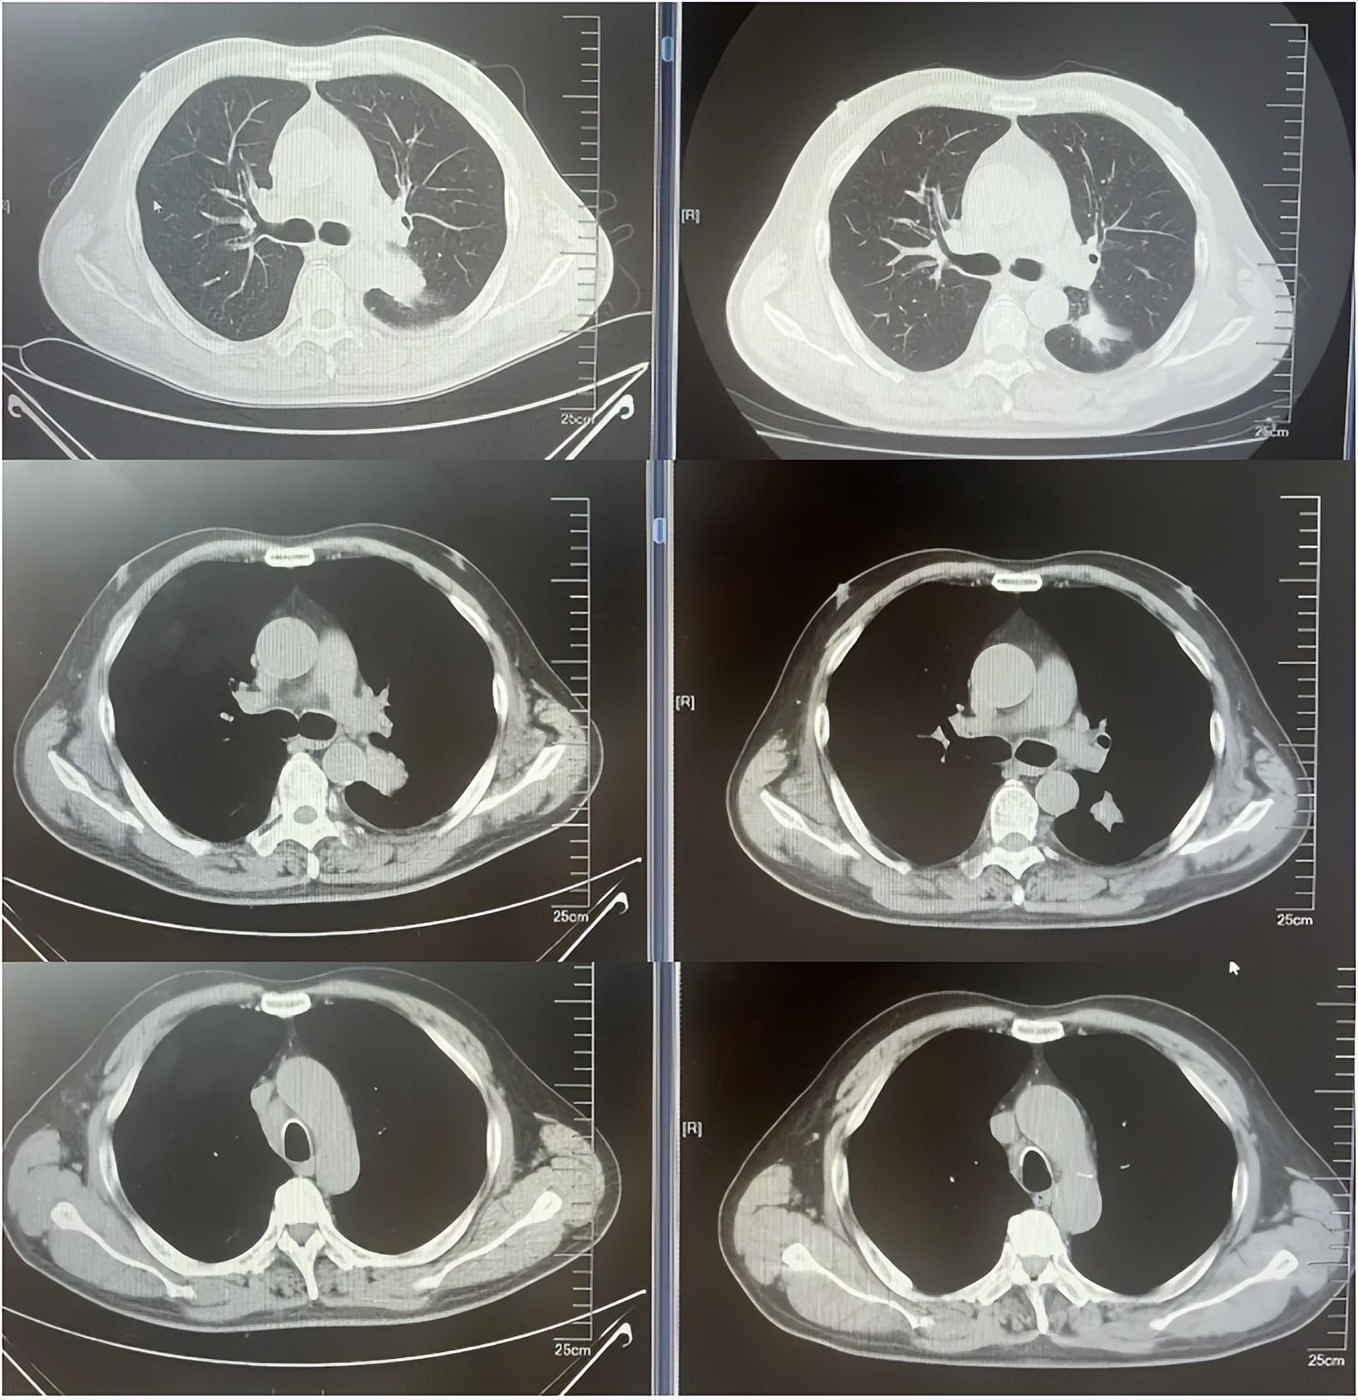

病例1:患者男,68岁。2024年6月以“胸闷气短1个月”为主诉于当地医院检查治疗。查CT提示左肺下叶肿物,纵隔、双肺门多发肿大淋巴结,左侧胸腔积液,左侧胸膜增厚。于当地医院行胸水穿刺引流查癌细胞提示肺腺癌。临床分期:cT2aN3M1a IVA期。患者于当地医院行血液基因检测未见敏感突变,使用AP方案化疗后病情进展。2025-1入我院后行肺穿刺活检,病例提示腺癌。行基因检测提示:ERBB2突变(丰度3.5%)。行德曲妥珠单抗(T-DXd)治疗至今。最佳疗效PR,目前持续有效中,PFS已超过7个月。患者使用德曲妥珠单抗期间出现II级恶心呕吐,经对症治疗可缓解。

德曲妥珠单抗治疗4周期(2025.5)疗效对比

德曲妥珠单抗治疗6周期(2025.7)疗效对比

德曲妥珠单抗治疗4周期(2025.4)疗效对比